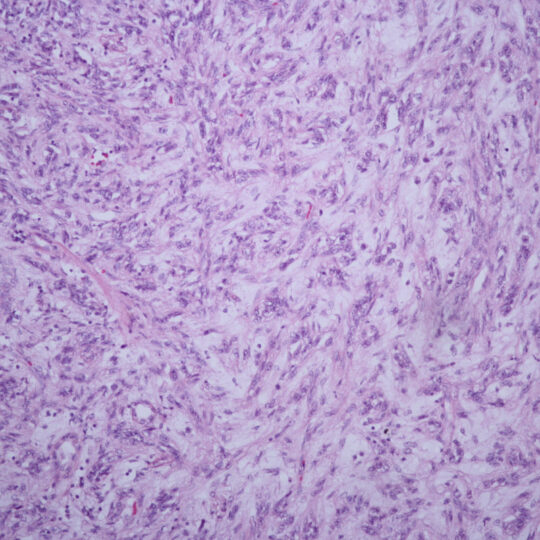

Na bioptickom úseku sa vykonáva štandardná diagnostika nádorových a nenádorových lézií rôznych orgánov, počnúc ochoreniami gastrointestinálneho traktu, ženského a mužského pohlavného systému, močového systému, ochorení hlavy a krku, nádorových ochorení CNS, kože, mäkkých tkanív a štítnej žľazy. Vyšetruje sa fixovaný materiál s použitím štandardných (HE), špeciálnych (Fe, PAS, Melaním VG, Ret…) a imunohistochemických farbiacich metód.

Väčší materiál spravidla vyžaduje dlhšiu dobu fixácie, čím sa predlžuje aj dĺžka trvania vyšetrenia, rovnako v prípade potreby ďalších vyšetrení ako sú rôzne špeciálne farbenia, imunohistochemické a molekulovo-genetické vyšetrenia.

Prípady vyžadujúce ďalšie náročné diagnostické postupy sú konzultované a riešené v spolupráci so špecializovanými pracoviskami v Martine a v Bratislave.